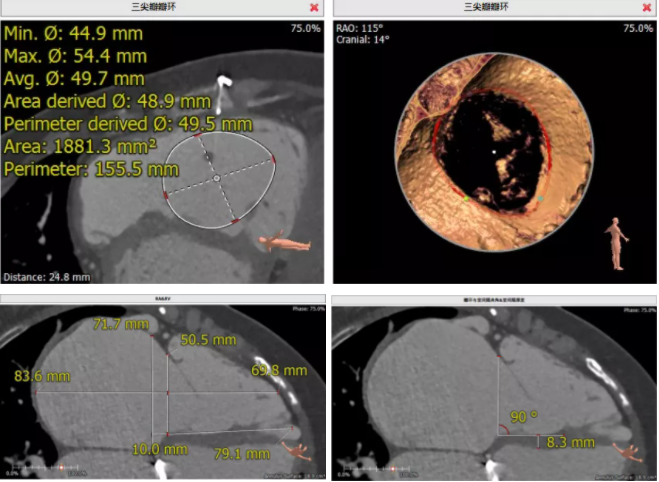

患者為68歲女性,14年前因“反復感冒、氣促”,檢查發(fā)現(xiàn)心臟瓣膜病,接受了“二尖瓣機械瓣置換術”。約5年前出現(xiàn)雙下肢水腫,活動后心累氣緊,心臟彩超提示:三尖瓣返流。近年來三尖瓣返流逐漸加重并伴有輕微黃疸、雙下肢水腫,雖長期服用利尿劑治療,但效果欠佳。郭惠明教授團隊結合病史、超聲及CT評估,考慮患者瓣膜置換術后,三尖瓣重度返流,再次開胸行體外循環(huán)手術風險高,經(jīng)團隊整體評估,決定采用最適合患者的LuX-Valve三尖瓣置換系統(tǒng)行微創(chuàng)治療,根據(jù)測量結果選擇植入JS/TTVI-28-55型號的LuX-Valve瓣膜。